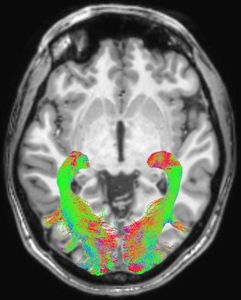

Sie sind hier: Startseite Nachrichten Gesundheit Parkinson: Visuelles System verändert sich früh Gehirn-Scan: Strukturen verändern sich frühzeitig. Bild: rsna.org

Gehirn-Scan: Strukturen verändern sich frühzeitig. Bild: rsna.org